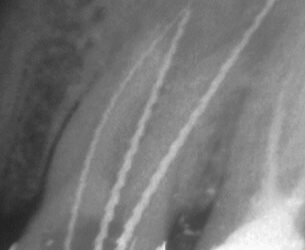

Nicht häufig gelingt es, einen Fistelverlauf sozusagen von der Quelle bis zur Mündung darzustellen wie in diesem kombinierten Endo-Par-Fall: In gleicher Sitzung erfolgte die großzügige Aufbereitung der drei auffindbaren Kanäle mit Überinstrumentierung, die...